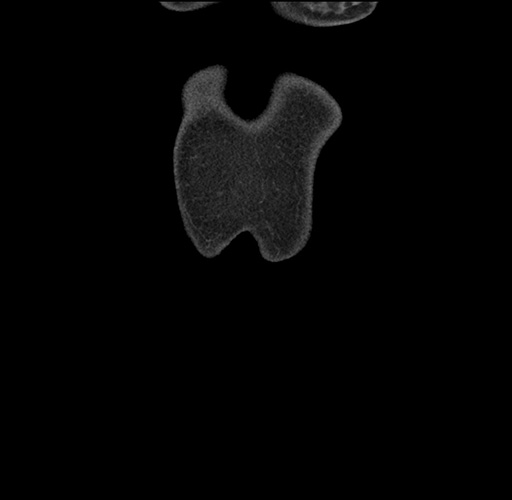

Imaging Analysis

Look through the patient's CT scan to identify any areas of concern for the necessary procedure.

Based on your CT findings, which issue(s) would give reason for "planned slowing down moment(s)" in this case?